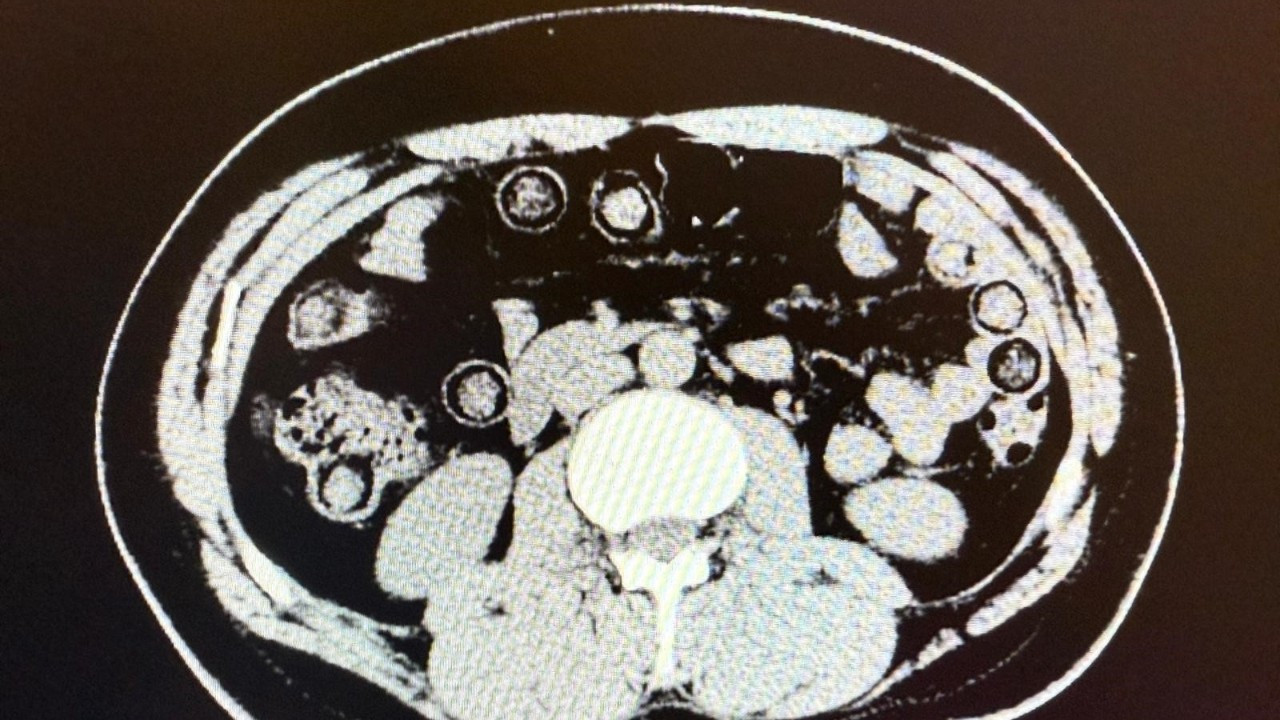

Hastanede yapılan tomografi görüntülerinde, şahısların midelerinde toplam 94 kapsül içinde 928 gram metamfetamin taşıdığı belirlendi. Kapsüller hastane ortamında çıkartılarak muhafaza altına alındı.